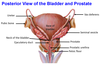

Postganglionic sympathetic fibers (they synapsed in the ganglion) leaving the sympathetic chain and joining a sacral nerve (S1). Will leave the pelvis with to go to the legs to nnervates blood vessels, sweat glands, hair follicules, etc.

Sacral splanchnic nerves - Preganglionic sympathetic fibers (they came down the chain) which will synapse in the inferior hypogastric plexus. They provide sympathetic innervation to the pelvic organs.